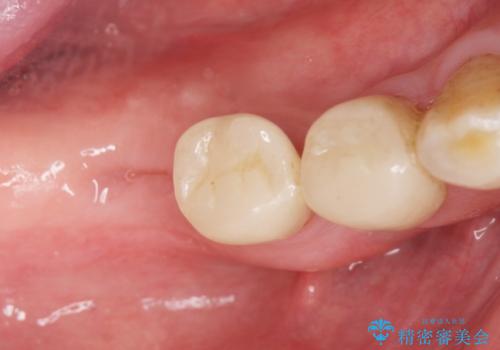

奥歯でしっかりと咬むことができるようになり、大変喜んで頂けました。

クラウンの種類:オールセラミッククラウン スタンダード